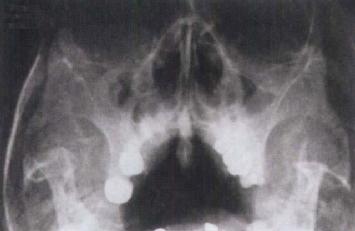

上颌牙龈扁平上皮癌